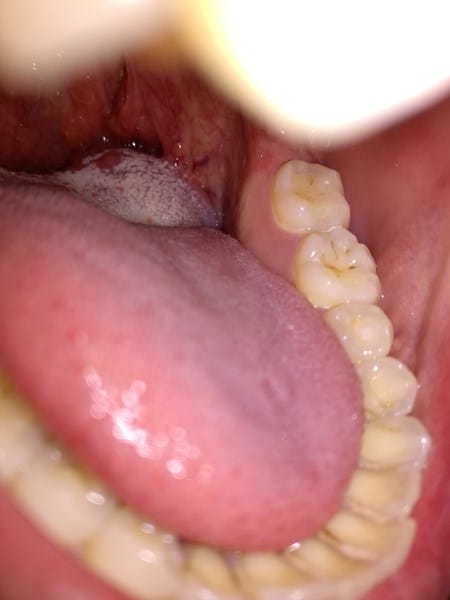

I. Hola Gemma, creo, según estoy leyendo, que podría tratarse de un cuadro de reflujo intestinal. (Acidez estomacal), La placa placa de color blanquecino por lo visto es conocida como 'saburra'.

"**SABURRA " Ese es el nombre de la capa blanca que cubre la zona posterior de tu lengua, es frecuente que sea abundante y gruesa en pacientes con reflujo gastroesofágico. Una de las formas de disminuirla es llevando una dieta sana sin excesos de grasas ni frituras, no comer nada dos horas antes de acostarse, evitar los aderezos como Ketchup y Mayo. Las infusiones de manzanilla caliente después de almuerzo son beneficiosas en resumen, dieta sana sin excesos de grasas, frituras y fibras como la de la cebolla o el ollejo de las legumbres, realizar deportes que fortalecen tu musculatura abdominal, tratar que los alimentos tengan una constitución más pastosa que liquida.**

hola soy angie tengo lo mismo de ella y he tomado mucho antibiotico y nada esas placas en la glandula derecha ya me hicieron examenes y negativos me van a repetir un examen pero se que va salir bien - Angely Rico

I.Hola Angie, lamento la situación, ojalá todo marche bien y encuentren pronto el motivo.Por desgracia en mi caso no sé qué mas podría comentar al margen de lo que expuse a la compañera, solicitar un cultivo/biopsia de la zona (muestra de tejido) es lo único que se me ocurre. - david ..